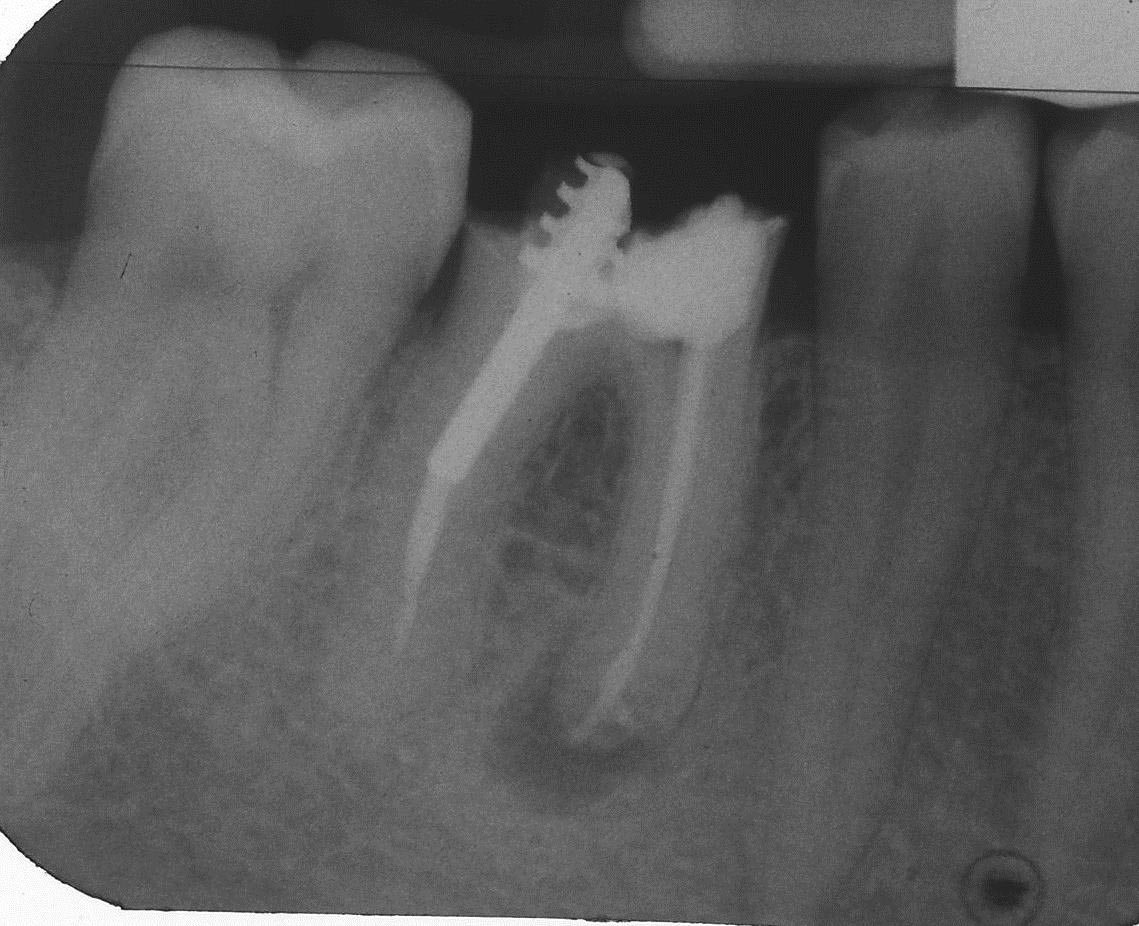

2 Teilrevision mesial, Masterpoint 15.09.2008 Veröffentlicht 6. Oktober 2013 am 1139 × 926 in Teilrevision Zahn 46 – Wie würden Sie entscheiden?